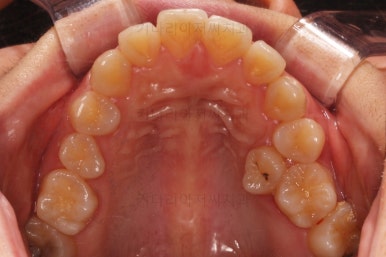

마찬가지로 부산연산동교정치과 초진 시 입안의 모습입니다.

눈에 띄는 것은 윗니 안쪽 치아 하나가 아예 입천장쪽으로 나서 매우 삐뚤어요.

저렇게 삼각혁으로 배치되어 있는 치아는 셋 중 하나는 꼭 썩어요.

셋 사이에 음식물이 잘 끼고 양치가 힘들기 때문이죠.